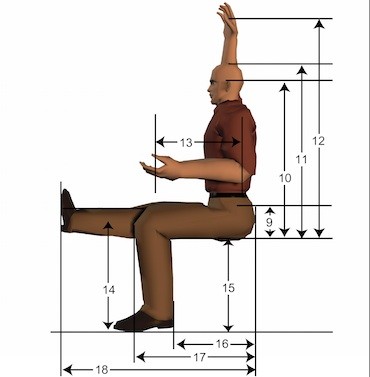

قیمت: 156٬000 تومان - دسته بندی فایل: پاورپوینتپاورپوینت ارزیابی آنتروپومتری

فروش ویژه ی پاورپوینت حرفه ای ارزیابی آنتروپومتری با تخفیف استثنایی فقط 123 هزار تومان تعداد اسلایدها: 105 اسلاید